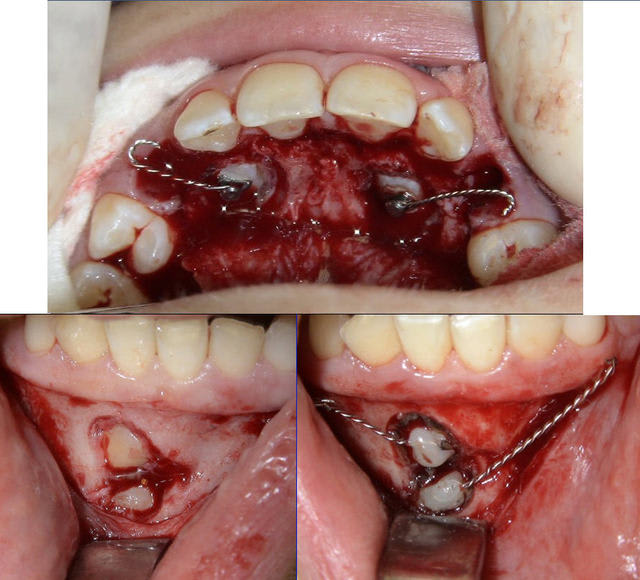

14 ans. C'est moi qui m'y colle mi-mai (dégagement chirurgical des couronnes et traction orthodontique).

Le haut, c'est banal.

Par contre pour le bas, c'est une autre histoire... Je ne vois pas d'autre solution que des ancrages osseux latéraux pour y arriver sans télescoper les racines des incisives. Haut les coeurs ! On y arrivera !

Un système que je développe moi-même depuis quelques années et qui a des possibilités d’évolution qui semblent infinies (Rev Orthop Dento Faciale 2006;40:63-90). Ici, j’ai utilisé deux vis de chirurgie maxillo-faciale en tandem sous muqueuses. Y est accroché un fil en TMA .018 qui émerge en latéral le long du vestibule et vient tracter, comme une « canne à pêche » la ligature qui est collée directement aux couronnes des canines incluses.

En haut, système plus banal (si j’ose dire).

> Les 4 en 1 séance?

Oui, au cabinet sous anesthésie locale. D’abord le haut, puis le bas.

Difficile à dire, cela m’étonnerait quand même que cela puisse être inférieur à 18 mois compte tenu de la position de la 33. Dès que les incisives inférieures seront dégagées, j’attaquerai le traitement orthodontique proprement dit.

4 canines chir qjsr4u - Eugenol

Seules différences : dans ce cas-ci j’ai quand même donné en final une couverture antibio, il y avait deux vis en tandem au lieu d’une et la canne à pêche ressemblait plutôt à cela (voir photo).

Daniel

Voici des photos prises 8 jours après l'intervention. RAS de particulier. A suivre !

4 canines 8jours ewocp6 - Eugenol